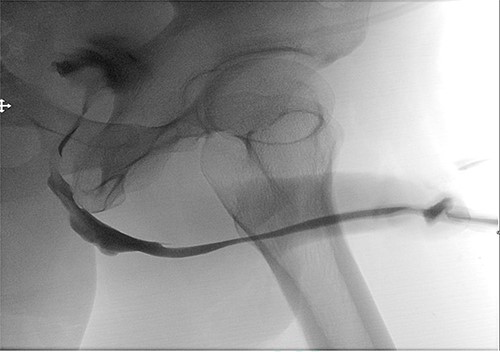

A 38-year-old male was referred to our tertiary hospital due to recurrent urethral stricture for further evaluation and management. His history revealed multiple failed attempts of DVIU, anastomotic urethroplasty and urethroplasty with pedicled fasciocutaneous flap in 2019. Nine months after his surgery, he had complete retention due to stricture recurrence and he underwent multiple dilatations and DVIU but his stricture keep recurring. He was referred to us for definitive management. He was on a suprapubic catheter. Initial workup included retrograde, antegrade cystoscopy and urethrogram. First, an antegrade cystoscope was introduced. The bladder neck, internal sphincter and verumontanum were identified. However, there was no external sphincter due to damage from the previous procedures. A pinpoint opening in the dorsal area of the urethra was seen about 1-cm distal to the verumontanum (Fig. 1, lumen A). Also, a blind-ended urethra in the ventral area was identified (Fig. 2, lumen B). It is most likely from the previous flap. Additionally, the retrograde urethrogram showed that the contrast was only going from the pinpoint hole in the dorsal side of the urethra Fig. 3. Retrograde cystoscopy also showed a blind-ended in the proximal bulbar urethra. We could not identify the small hole that we saw from the antegrade cystoscopy. After initial workup, he was counseled in the clinic for dorsal only buccal mucosal graft (BMG) urethroplasty for which he agreed.

Antegrade (3–1) and retrograde (3–2) urethrogram showing the contrast passing through the pinpoint hole in the dorsal side of the urethra as pointed in black arrow, lumen A; antegrade (3–1) and retrograde (3–2) urethrogram showing a blind ended urethra in the ventral side of the urethra as pointed in red arrow, lumen B.